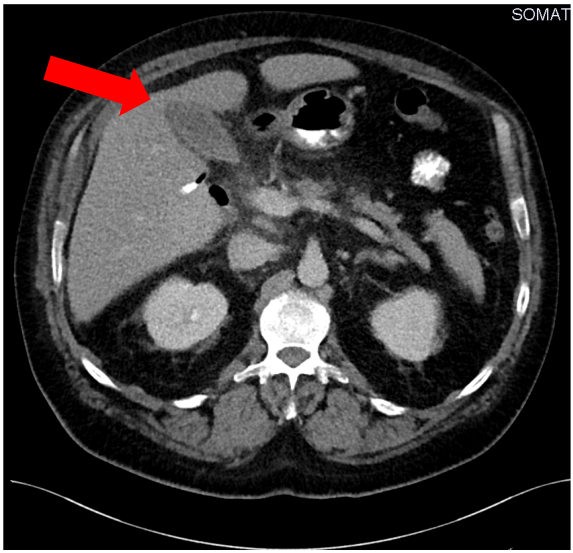

In the following days the patient’s situation destabilized showing clinical signs and symptoms auf acute abdomen. An abdominal CT scan on the ninth day after initial admission revealed a perihepatic abscess (Figure 1 [Fig. 1]). This was treated with immediate surgical intervention and drainage of the hepatic abscess by visceral surgeons of our hospital. An additional microbiological examination of the hepatic abscess material confirmed the contamination with Eggerthia catenaformis. Postoperatively, the patient received another three erythrocyte concentrate transfusions (500 ml each) and 2000 IE prothrombin complex to treat persistent anaemia and ethyl-toxic blood coagulation disorder.

Figure 1: Preoperative computed tomography of the hepatic abscess (red arrow)